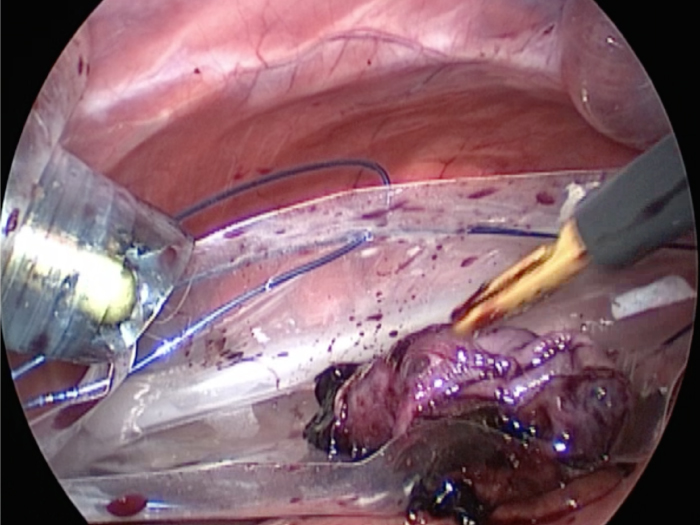

胆嚢が破裂した様子を腹腔内にカメラを入れて観察した像です。

胆嚢から漏れ出た胆汁が腹腔内に確認できます

体の外に出すためお腹の中で袋に入れていきます。

このときに胆嚢と一緒にクリップやガーゼも回収します。

そしてお腹の中をきれいにしていきます。